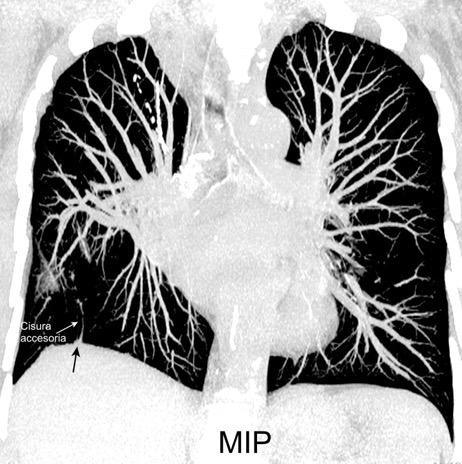

25. ELEVACIÓN UNILATERAL. TEP

Tromboembolismo pulmonar Diafragma elevado 20%